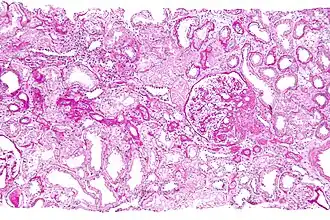

![]() Micrograph showing a renal core biopsy. PAS stain. | |